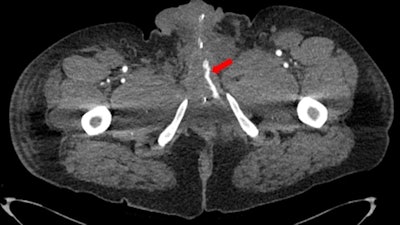

In some cases of penile trauma (e.g., a traumatic arteriolacunar fistula), CT can be of value.